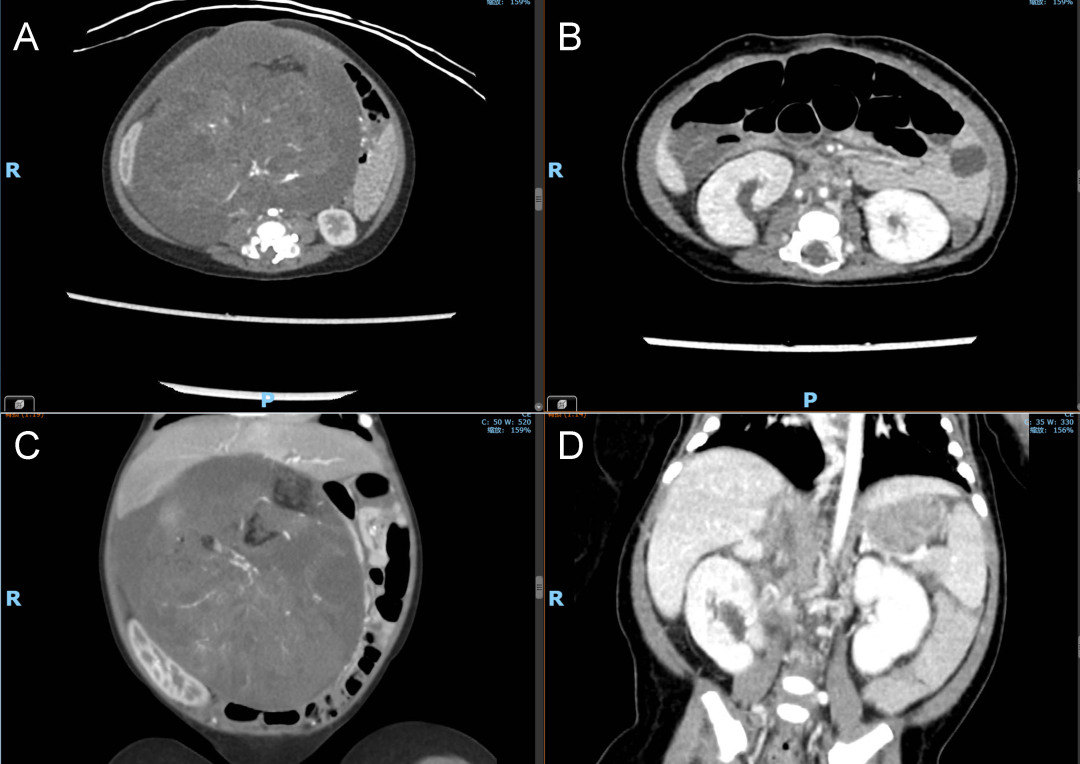

图3:患儿术前和术后腹腔CT对比。A-B,术前和术后腹腔CT横截面对比,提示腹腔内巨大肿瘤成功切除后双肺压迫得到了显著的改善;C-D,术前和术后腹腔CT冠状面对比,提示腹腔内巨大肿瘤成功切除后双肾等腹腔脏器压迫得到了显著的改善。